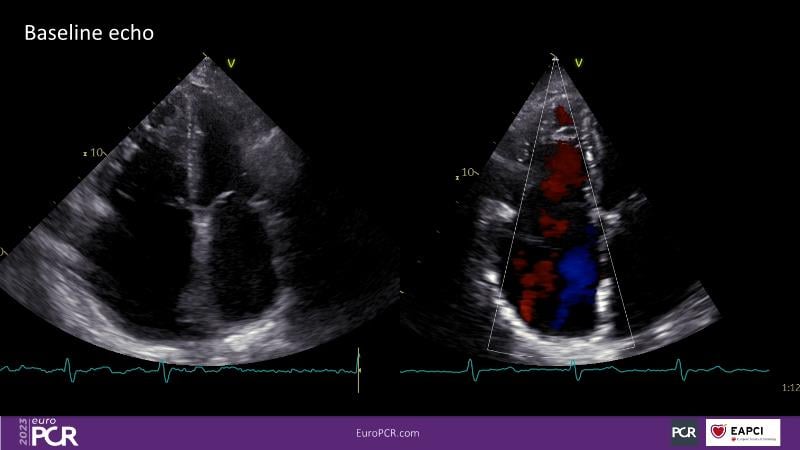

Watch this session to discuss exciting cases of tricuspid regurgitation, learn about the proposed new integrated classification for tricuspid regurgitation and enjoy a live presentation of the PASCAL Precision Repair System using a beating heart simulator, among others!

- To discuss the different tricuspid regurgitation phenotypes that can be treated with the PASCAL Precision repair system

- To participate in a case-based discussion using the PASCAL Precision repair system for the treatment of tricuspid regurgitation